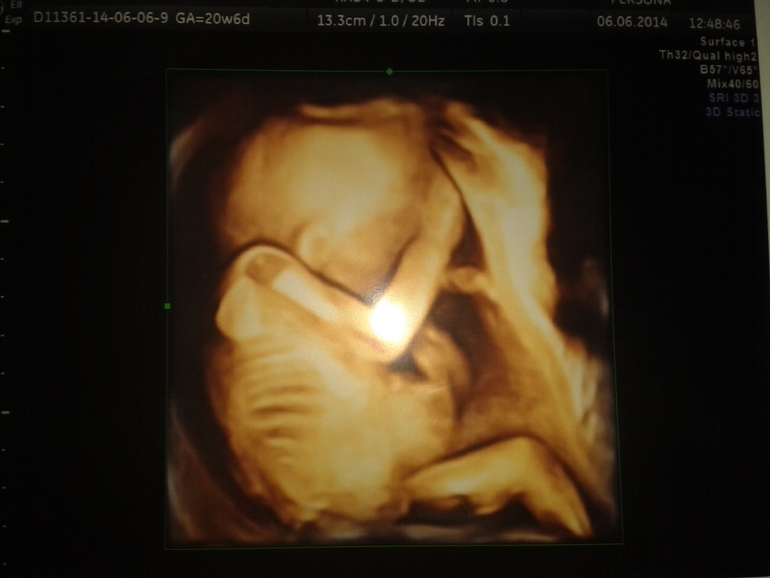

Привет, девочки!))Моей принцессе 20 неделек и два дня.))Мы были на узи позавчера и оьсуждали там наш плоский ровный живот при нормальном развитии малышки, и отсутствие явных шевелюшек при видимой активности на УЗИ...а вчера я проснулась от толчков)))Подошла к зеркалу,а там...видимо ко дню рождения папули торопились)))

Девочки!))Мы с мужем вместе сходили, малышке 20 недель))Несмотря на крохотный живот и отсутствие набора веса,малышка моя прекрасно себя чувствует, никакого маловодия у меня нет,всё ттт отлично!))Сидит спинкой повернута, удобно ей так.)))Ну это еще нестабильно, они еще вертятся на таком сроке гиперактивно)))Все мои страхи рассеены)))И всё таки там доченька, как и предположили на 1 скрининге))Принцесса моя маленькая)))Несмотря на отсутствие у меня явных шевелюшек по ощущениям, я смогла наблюдать как она там вертится!))Всё таки,как обьяснил врач,плацента по передней стенке чувствительность занижает.))Как я рада, что всё как надо!)))